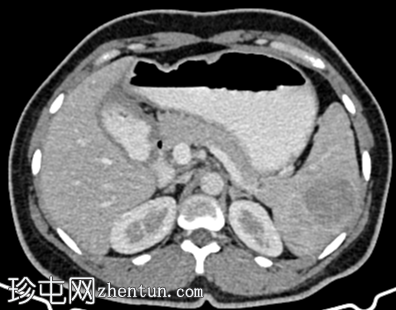

轴位增强扫描

动脉期

脾脏内可见一圆形低密度病灶,动脉期呈周边环状强化,延迟期呈轻微向心性充盈

未见钙化、动静脉畸形或动脉瘤

学特征为:病灶周围呈放射状强化,中心呈放射状强化,周围环状强化,中心充盈轻微。增强扫描后可见中央星状瘢痕。